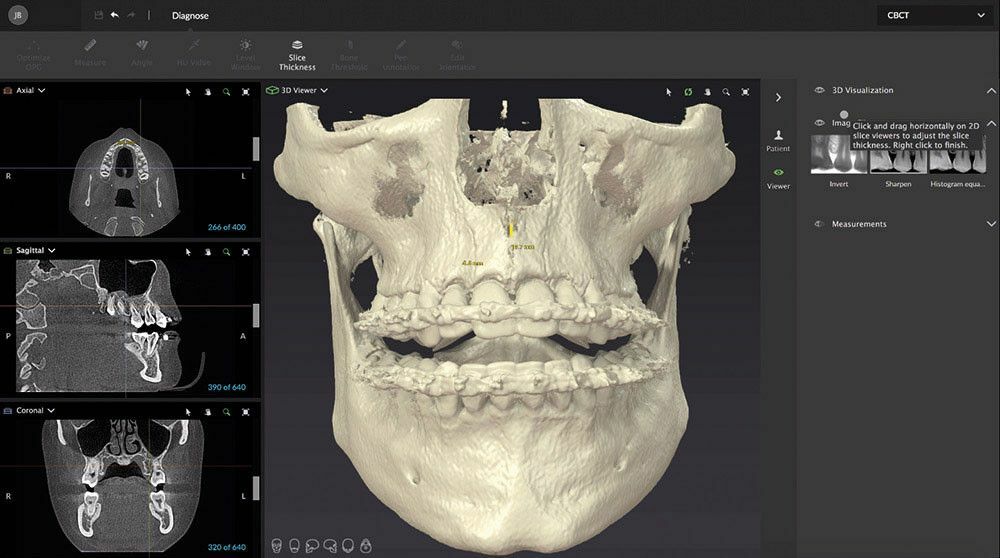

Необходимое вам для работы ПО будет установлено во время монтажа аппарата KaVo OP 3D Vision. В перечне предустановленного программного обеспечения есть все необходимы функции: поддержка трехмерной рентгенографии, программа планирования имплантации и другие функции.

Ваша рентгенографическая система KaVo OP 3D Vision готова для будущей эксплуатации нового комплексного программного обеспечения DTX Studio: вы cможете заказать DTX Studio, новую программную платформу, разработанную в виде целостной системы организации технологических процессов. DTX Studio постоянно оптимизируется и охватывает все области современной стоматологии и будущих дентальных технологий. DTX Studio совместимо с операционными системами Mac и Windows. Оно будет объединять как уже существующие, так и проектируемые устройства многочисленных брендов, а также современные возможности программного обеспечения в единный рабочий процесс.